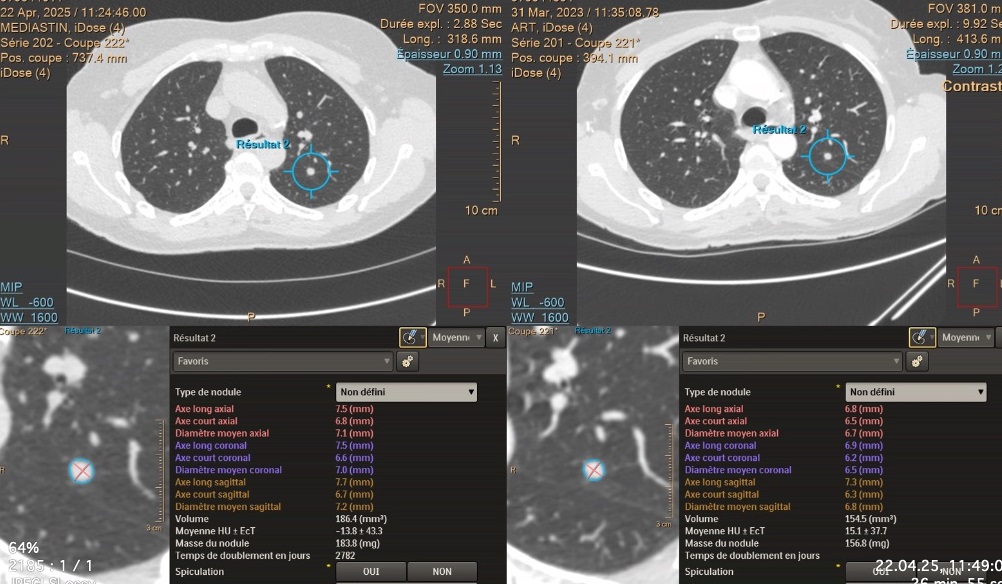

CT-scan thoracique low-dose. Il permet, entre autres, d’obtenir des images 3D, de visualiser le parenchyme pulmonaire et de surveiller l’évolution des nodules éventuellement malins.